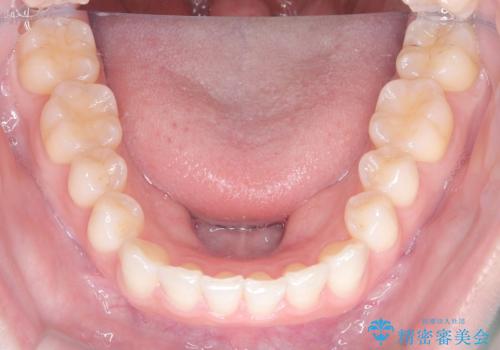

- 前歯のガタガタが気になるとのことでご相談いただきました。診察すると、歯列のスペースが不足し、前歯が重なっている状態でした。抜歯をせずに整えるため、歯と歯の間をわずかに削るIPR(歯列幅径削除)と、奥歯を後方へ動かす遠心移動を組み合わせてスペースを確保しながら並べる治療計画を立てました。

インビザラインを用いて歯を少しずつ移動させながら、IPRで微調整を行い、スペースを確保しました。また、奥歯を遠心移動させることで、前歯を自然な位置に並べることができました。治療後は、「ガタガタがなくなり、スムーズな歯並びになった」と患者様にもご満足いただきました。